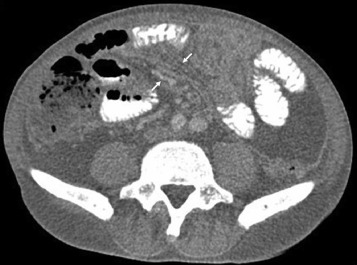

A 64-year-old man presented with abdominal fullness and intermittent night fever for 1 month. His medical history included hemodialysis for 1 year and hypertension. He did not drink alcohol and had no history of chronic hepatitis B or hepatitis C virus infection. There was no body weight loss, cough, or bowel habit change. His physical examination revealed abdominal distension and shifting dullness on percussion. Laboratory workup revealed anemia (hemoglobin, 8.4 g/dL) and hypoalbuminemia (albumin, 2.8 g/dL). The chest radiograph was normal. An abdominal computed tomography with contrast showed ascites, smooth uniform thickening of the peritoneum (arrowhead), omental cakes (arrow; Fig. 1 ), and soft tissue strands with crowded vascular bundles in the small bowel mesentery (Fig. 2 ). The ascitic fluid was cloudy yellow; the analysis revealed a white blood cell count of 950 cells/mm3 with 67% lymphocytes and a total protein level of 4.73 g/dL. Ascitic fluid culture, cytology, cell block, and acid-fast stain yielded negative results.

Contrast-enhanced computed tomography (CT) scan. Note the crowded vascular ...

Contrast-enhanced computed tomography (CT) scan. Note the crowded vascular bundles in the small bowel mesentery.